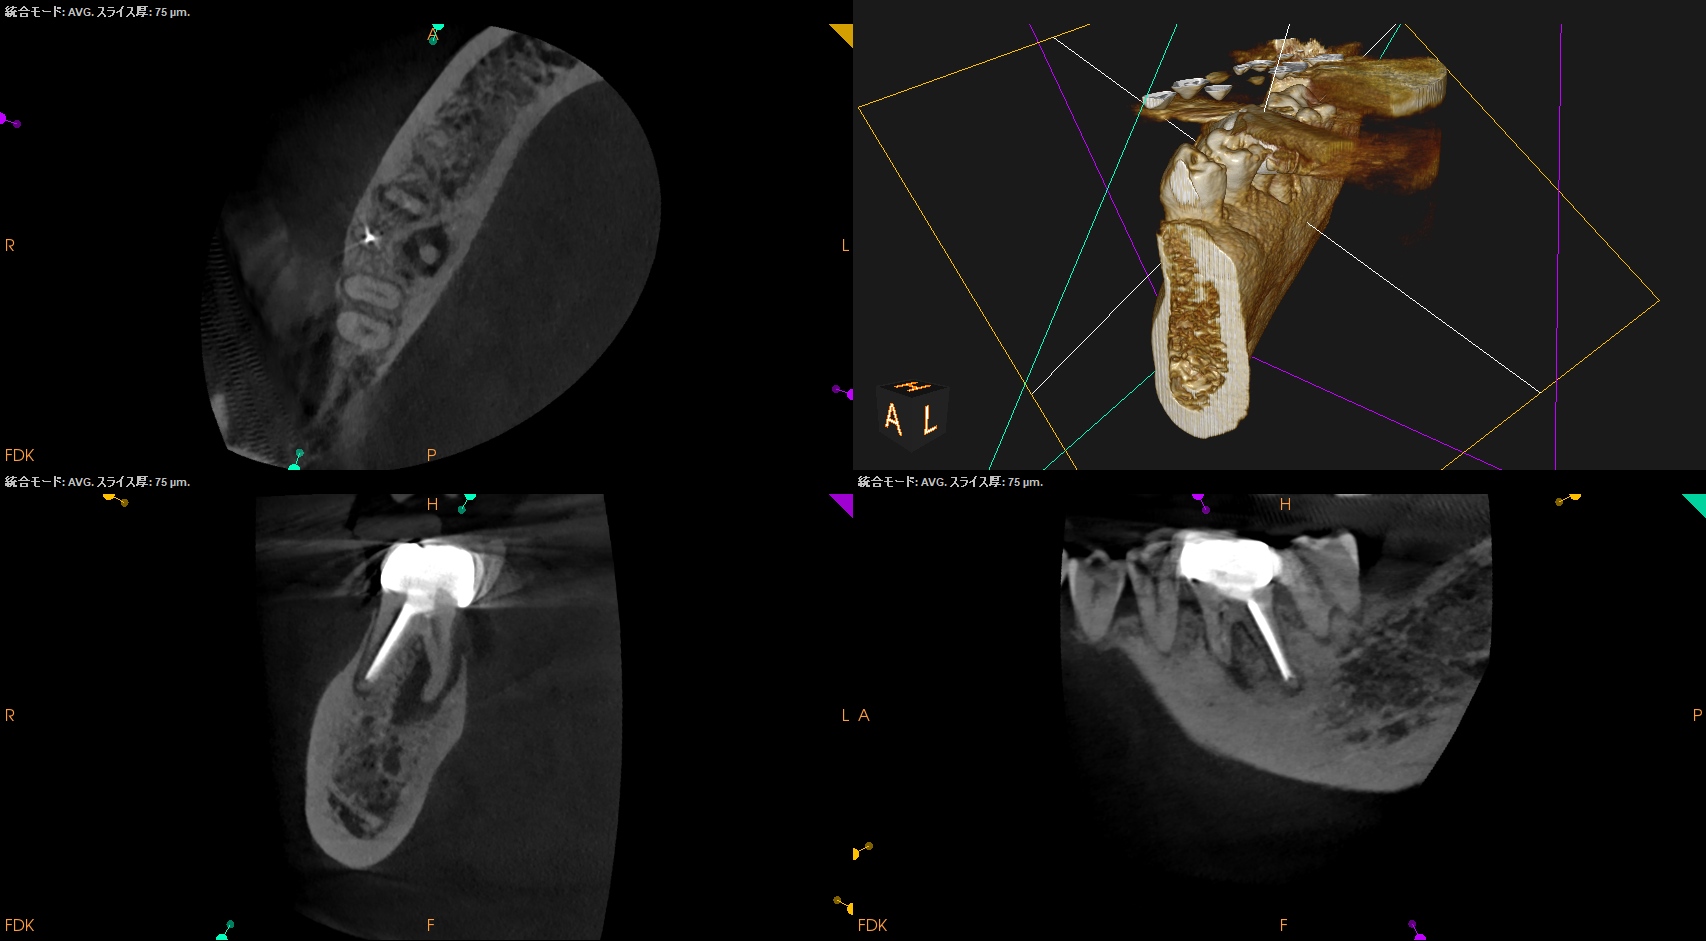

そこそこ湾曲度合いが強いRadix Entomolarisを有する#30だ。

が、D以外の根管はほぼ適切な根管治療がなされていない。

Radixにおいては未着手だ。

支台築造後にPA, CBCTを撮影した。

MB

ML

D

Radix

問題はないだろう。